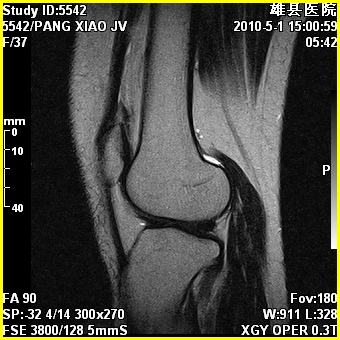

右股骨下端前内侧类圆形异常信号,位于干骺端,呈长t1长t2改变,但信号不均,t1图上病灶中心见小片状稍高信号影,t2图上见散在稍低信号影,stir像呈高信号,因病灶较小,缺乏特征性改变,结合患者年龄及部位,考虑嗜酸性肉芽肿可能性大。胫骨关节面下的小囊状异常信号,如果一元论考虑则为嗜酸性肉芽肿,不过发生在这个部位的少见,二元论考虑为邻关节骨囊肿。半月板与前后交叉韧带均未见异常。